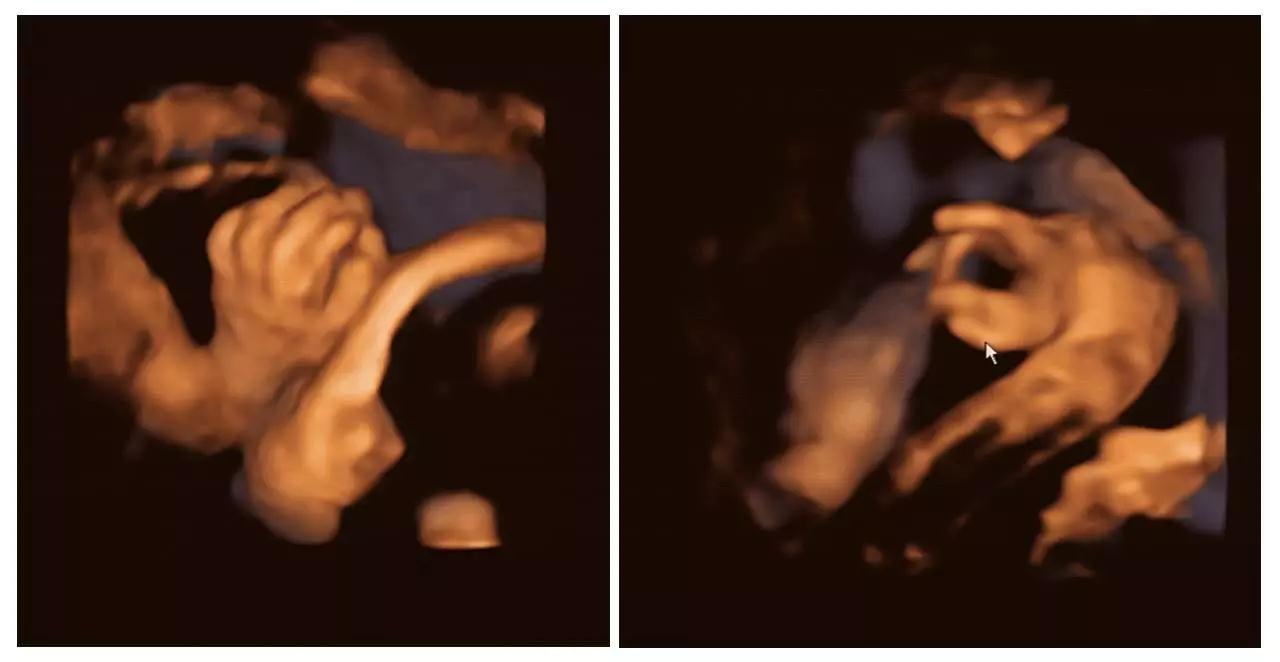

美GE不仅能提供包括腹部、血管、小器官、产科、妇科、泌尿科、新生儿和儿科等多领域的多方面的应用,而且能够显示未出生的宝宝的实时动态活动图像,为胎儿进行宫内拍“写真”和动态录像,让宝宝拥有完整的0岁相册。通过四维彩超(四维彩超),可以看到宫内胎儿打哈欠、伸懒腰、吮手指等萌萌的动作,让准爸妈们增添了安心和乐趣,不再仅仅是感觉宝宝的呼吸和运动,可以亲眼目睹宝宝的举动和乖巧容颜。还可以打印宫内高清写真,作为送给未来宝宝的珍贵礼物!

(右手多指畸形)